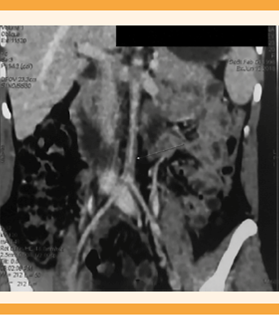

Paciente de 21 años, sin antecedentes familiares de importancia, originaria y residente de Piedras Negras, Coahuila, de ocupación estudiante. Grupo y Rh O+. Antecedente de linfoma de Hodgkin tipo nodular escleroso, EC IIA Bulky, diagnosticado en 2016 y tratada con 8 ciclos de quimioterapia (clorhidrato de doxorrubicina, sulfato de bleomicina, sulfato de vinblastina y dacarbazina) y 20 sesiones de radioterapia, la última en febrero del 2018. Como parte del seguimiento se le practicó una tomografía por emisión de positrones multicorte, sin evidencia de actividad tumoral. El hallazgo radiológico fue de concentración del radiofármaco de manera circunferencial en la aorta, en todo su trayecto, con SUVmax de 2.0, asociado con placas ateromatosas mixtas (Figura 1). Además, engrosamiento circunferencial de la íntima, de localización infrarrenal, que condicionó la disminución de la luz mayor de 95%, antes de su bifurcación (Figuras 2y3). Se trató con ácido acetilsalicílico y pravastatina.

Figura 3 Disminución de la luz de la aorta abdominal mayor de 95% antes de su bifurcación. (Flecha con punta blanca).